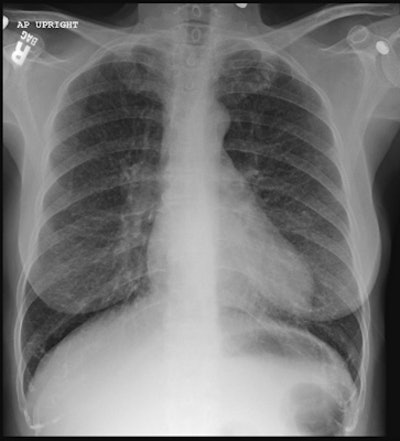

CXR demonstrated normal to large lung volumes with prominent reticular markings (click image to enlarge) |